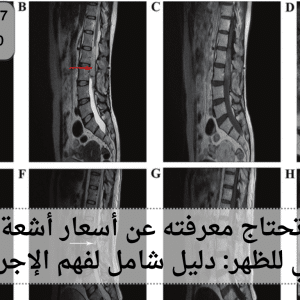

تعد مركز للأشعة اليوم من الركائز الأساسية في أي منظومة طبية حديثة، إذ لا يمكن لأي مستشفى أو عيادة متخصصة أن تعمل بفعالية من دونها.

أشعة الرنين المغناطيسي للظهر تعد واحدة من أكثر الوسائل الطبية دقة في تشخيص أمراض العمود الفقري والمشكلات العصبية المرتبطة به. في عصرنا الحديث، أصبحت هذه

يعد جهاز الرنين المغناطيسي المفتوح من أبرز الابتكارات الطبية الحديثة التي أحدثت ثورة في عالم التصوير الطبي. إذ يوفّر هذا الجهاز تجربة أكثر راحة وسلاسة